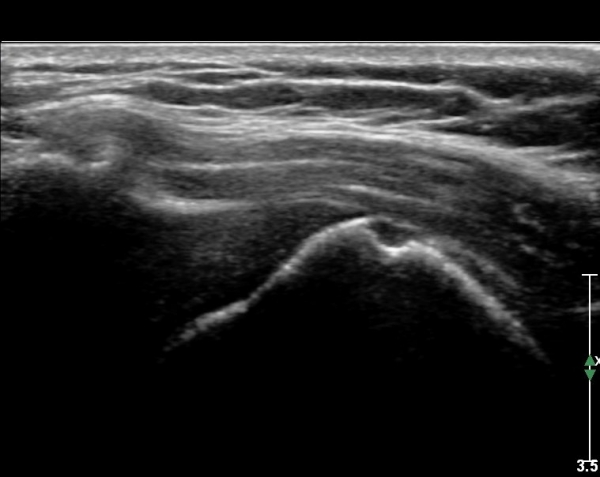

Å½ÃËÀÚ¸¦ Á»´õ ¸»´ÜÀ¸·Î À̵¿ ÈÄ(¶Ç´Â ¾Æ·¡·Î ±â¿ïÀÎ ÈÄ) ³»ÃøºÎ¸¦ Á¶ÀýÇÏ´Ï °ß°©ÇϱٰÇ

Ç¥ÃþÀ¸·Î Á¡¾×³¶³» ¼ö¾×Àú·ù°¡ °üÂûµÈ´Ù(»çÁö 3, 4). ŽÃËÀÚ¸¦ Á¶Á¤ÇÏ´Ï ÀÌµÎ¹Ú°Ç ÁÖÀ§ ¼ö¾× Àú·ù¿Í

Á¡¾×³¶³» ¼ö¾×Àú·ù°¡ °üÂûµÇ¾î Á¡¾×³¶¿°°ú Ȱ¾×¸·¿°ÀÌ ÀÖÀ½À» ¾Ë ¼ö ÀÖ´Ù(»çÁø 5).